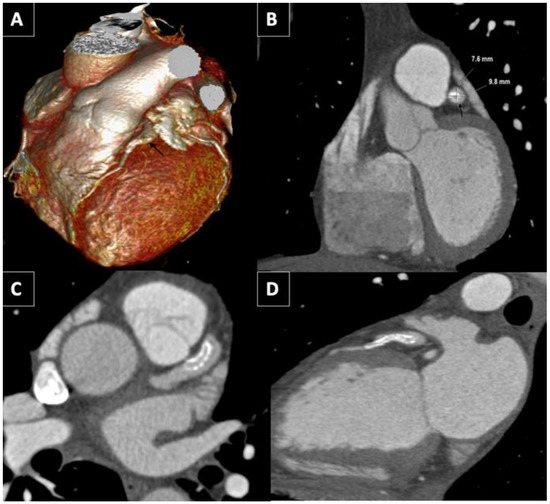

Coronary artery aneurysm (CAA) presenting as an ST-elevation myocardial infarction (STEMI) represents a clinical challenge due to the technical difficulties in the percutaneous management of this specific situation. Appropriate treatment for CAA depends on the precise clinical situation and consists of medical management, [...] Read more.

Coronary artery aneurysm (CAA) presenting as an ST-elevation myocardial infarction (STEMI) represents a clinical challenge due to the technical difficulties in the percutaneous management of this specific situation. Appropriate treatment for CAA depends on the precise clinical situation and consists of medical management, surgical resection, or/and stent placement. The high rate of complications during percutaneous intervention (distal thrombus embolization, no-reflow phenomenon, stent malposition, or dissection) makes emergent surgery a frequent situation in these cases. We present the case of a 50-year-old man with a STEMI due to thrombotic occlusion of CAA. Specific angiographic techniques and intracoronary imaging help with the percutaneous management of acute thrombotic occlusions in CAA, providing a less invasive approach than emergent surgery. Full article

Show Figures

Figure 1